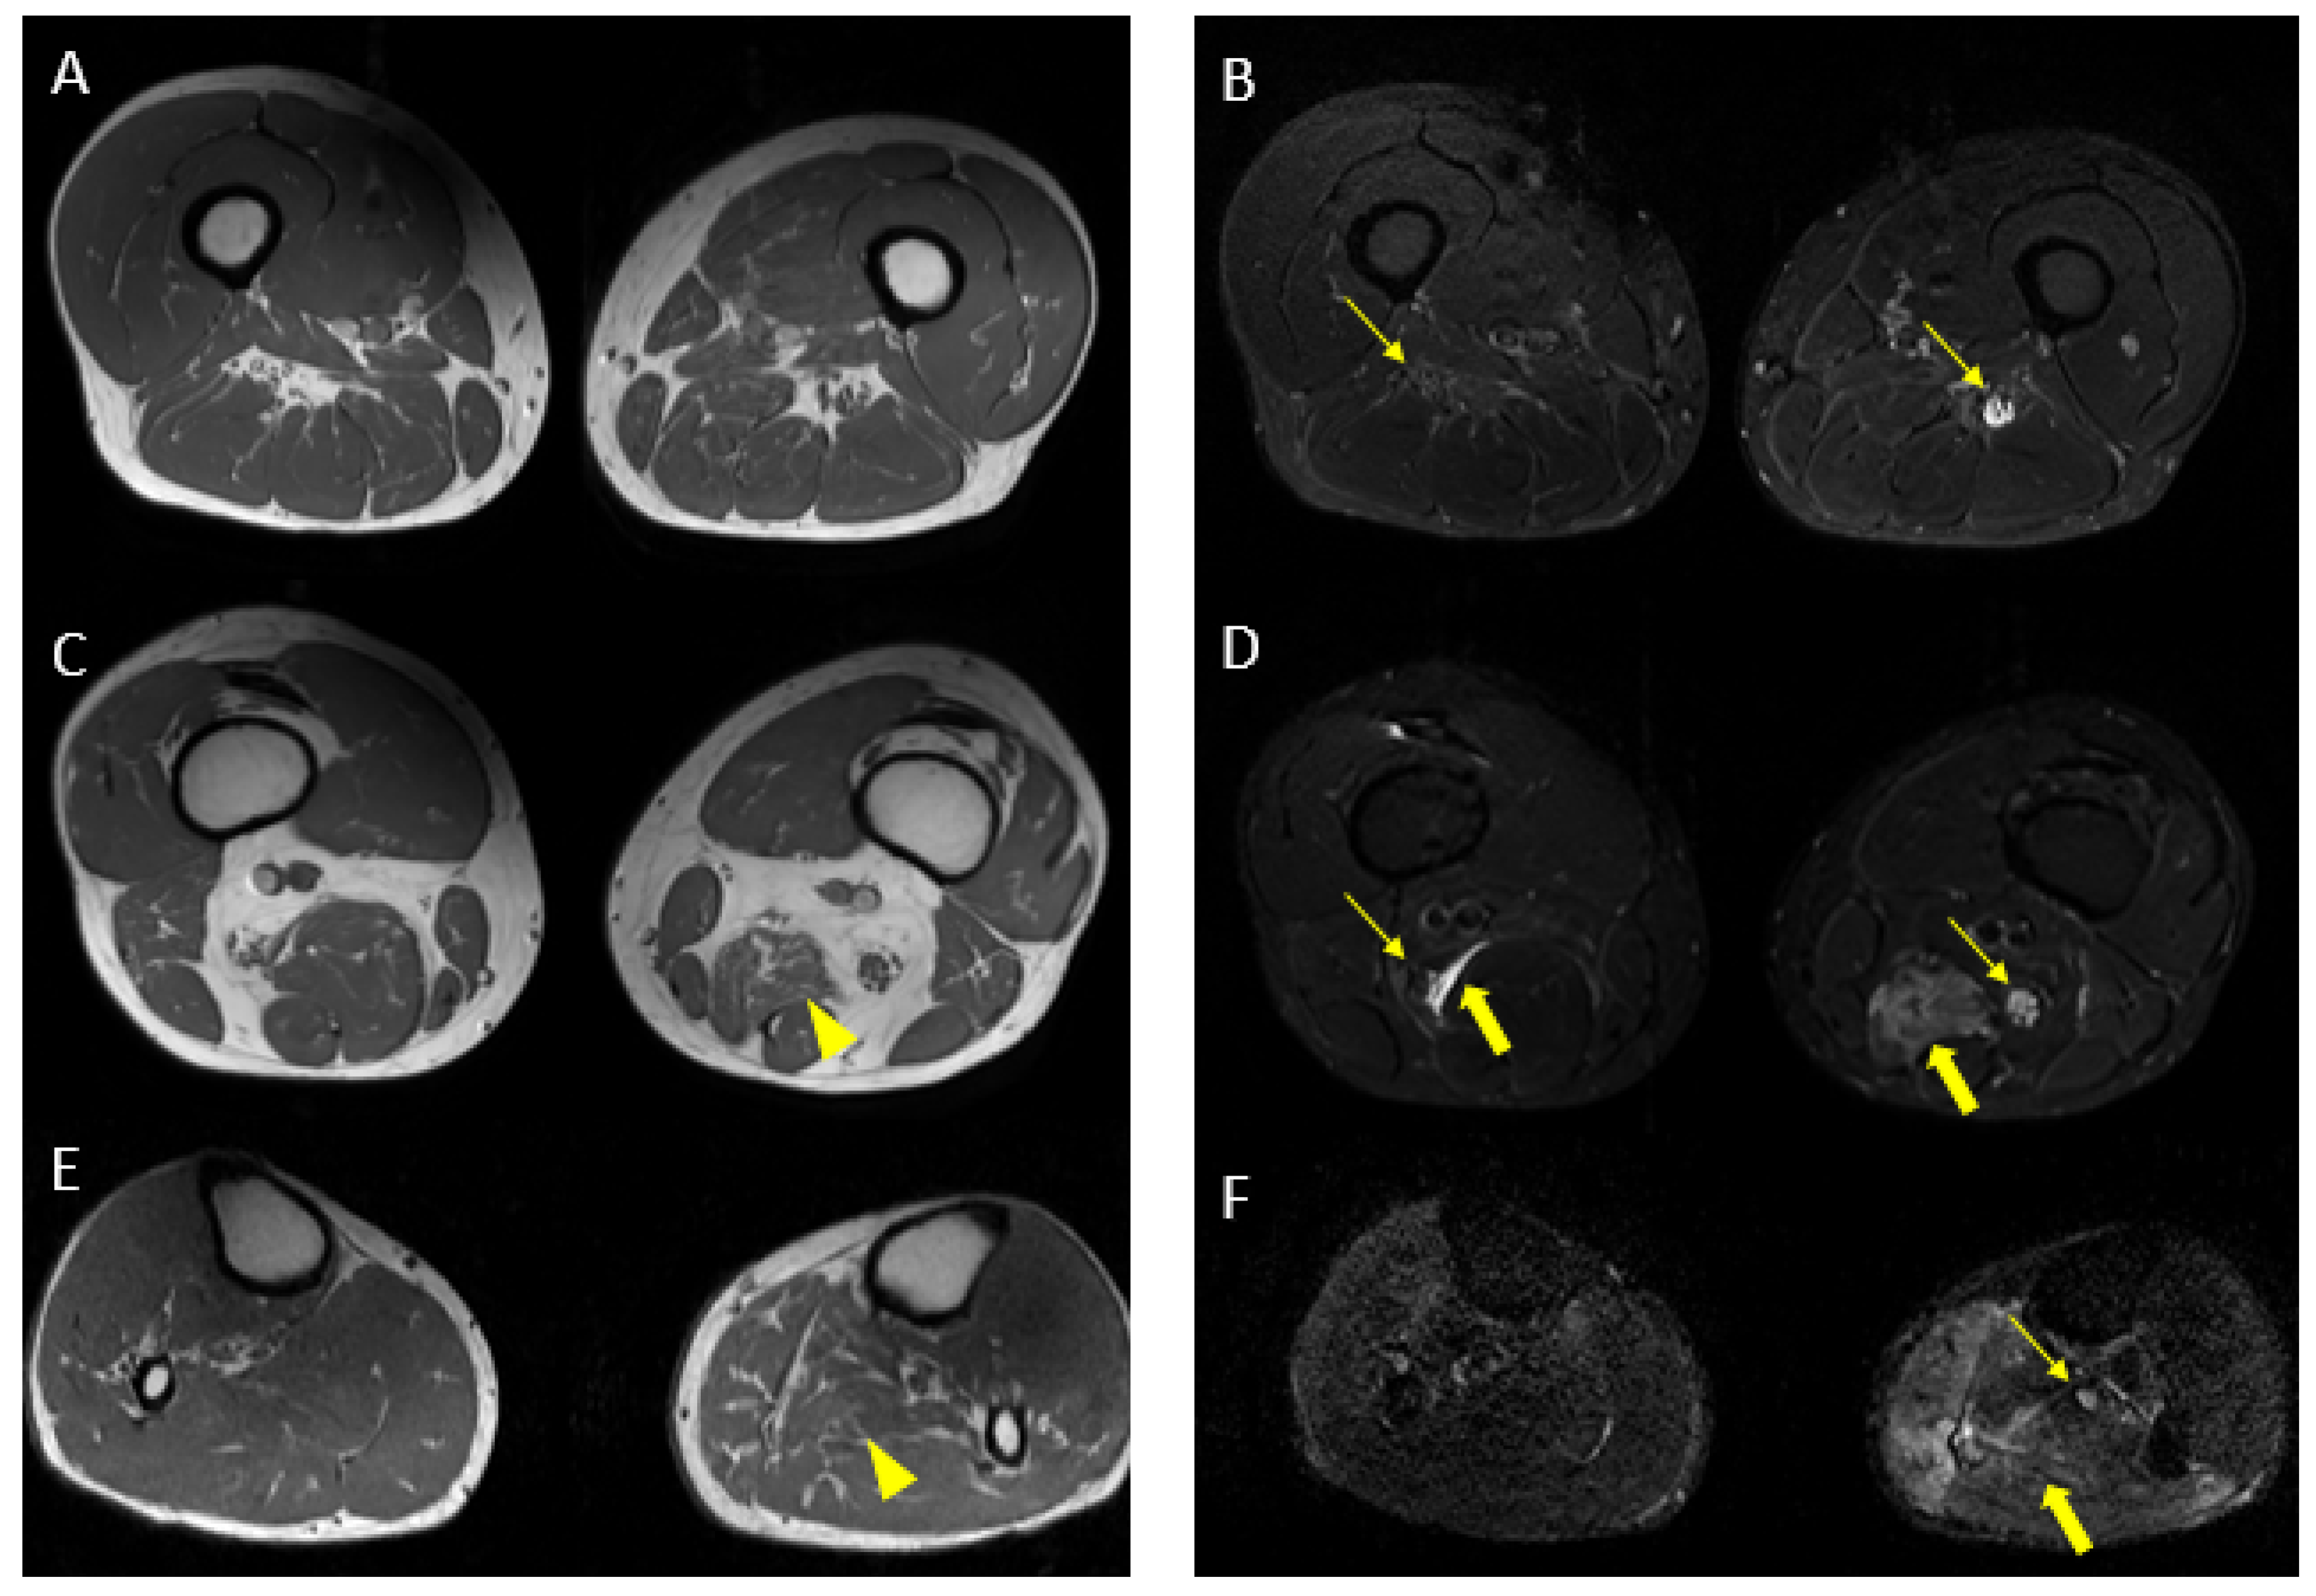

Figure 7.

Axial 2D MR of sciatic nerve; on the left are the T1w images and on the right are the T2 STIR images. Bilateral and symmetrical sciatic nerve T2 enlargement and fascicular hyperintensity at the level of the gluteal region (thin arrows (B); CSA of sciatic nerve of 103 mm2 on the right; 90.1 mm2 on the left) and at the mid-thigh (thin arrows in (D,F)). Mixed, acute and chronic denervation of the muscles of the anterolateral compartment of the thigh with denervation edema (hyperintensity in STIR, arrowheads in (D,F)) and fat replacement (thick arrows in (C,E)). Mainly chronic denervation of the gluteal muscles (hyperintensity in T1w, thick arrows in (A)).

Interpretation: The MR findings are consistent with the amyloid deposits between the fascicles of the sciatic nerve, supporting the clinical diagnosis.

MR findings: regular size and signal intensity of lumbar and sacral roots (Figure 6). Bilateral and symmetrical sciatic nerve T2 enlargement and fascicular hyperintensity (Figure 7). Mixed acute and chronic denervation of the muscles of the anterolateral compartment of the thigh. Mainly chronic denervation of the gluteal muscles (Figure 7).